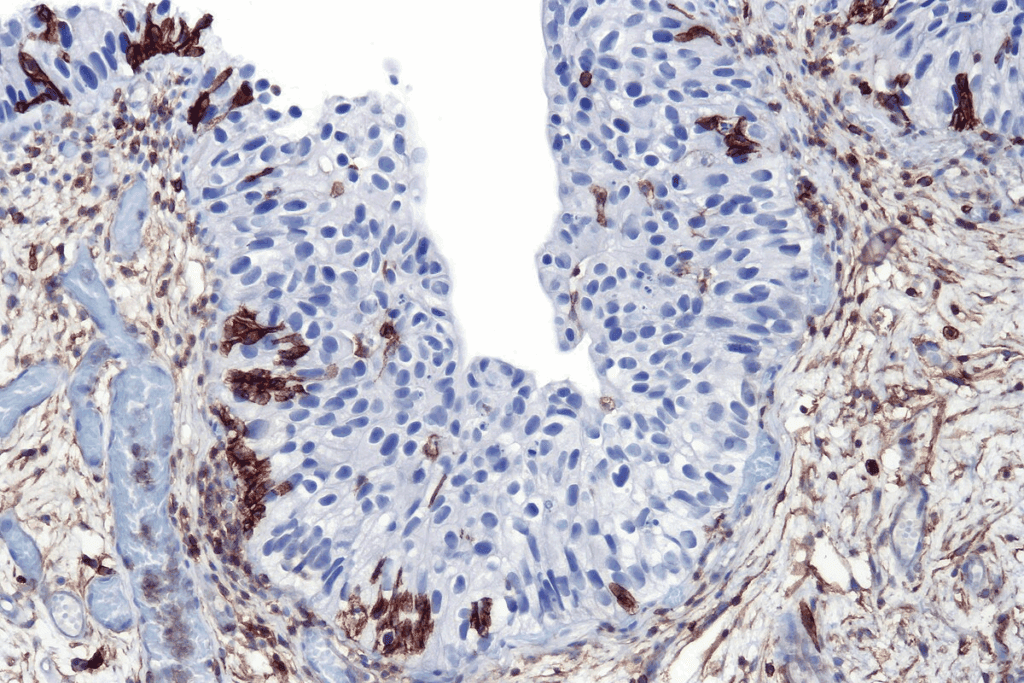

Carcinoma in situ has cancer cells that haven’t crossed the basement membrane. This membrane is a key barrier between cells and tissue. These cells look different from normal cells under a microscope.

Doctors diagnose carcinoma in situ by looking at these cell changes during a biopsy. These changes can range from mild to severe, showing how abnormal the cells are.

Carcinoma in situ also has specific molecular markers and genetic factors. These help predict how the condition might progress. They show if it could turn into invasive cancer.

Looking at tissues under a microscope is the best way to diagnose CIS. It confirms CIS and tells it apart from invasive cancer.

It checks the cells and how they are arranged. Histological grading and molecular markers give more info on how likely the cancer is to grow.